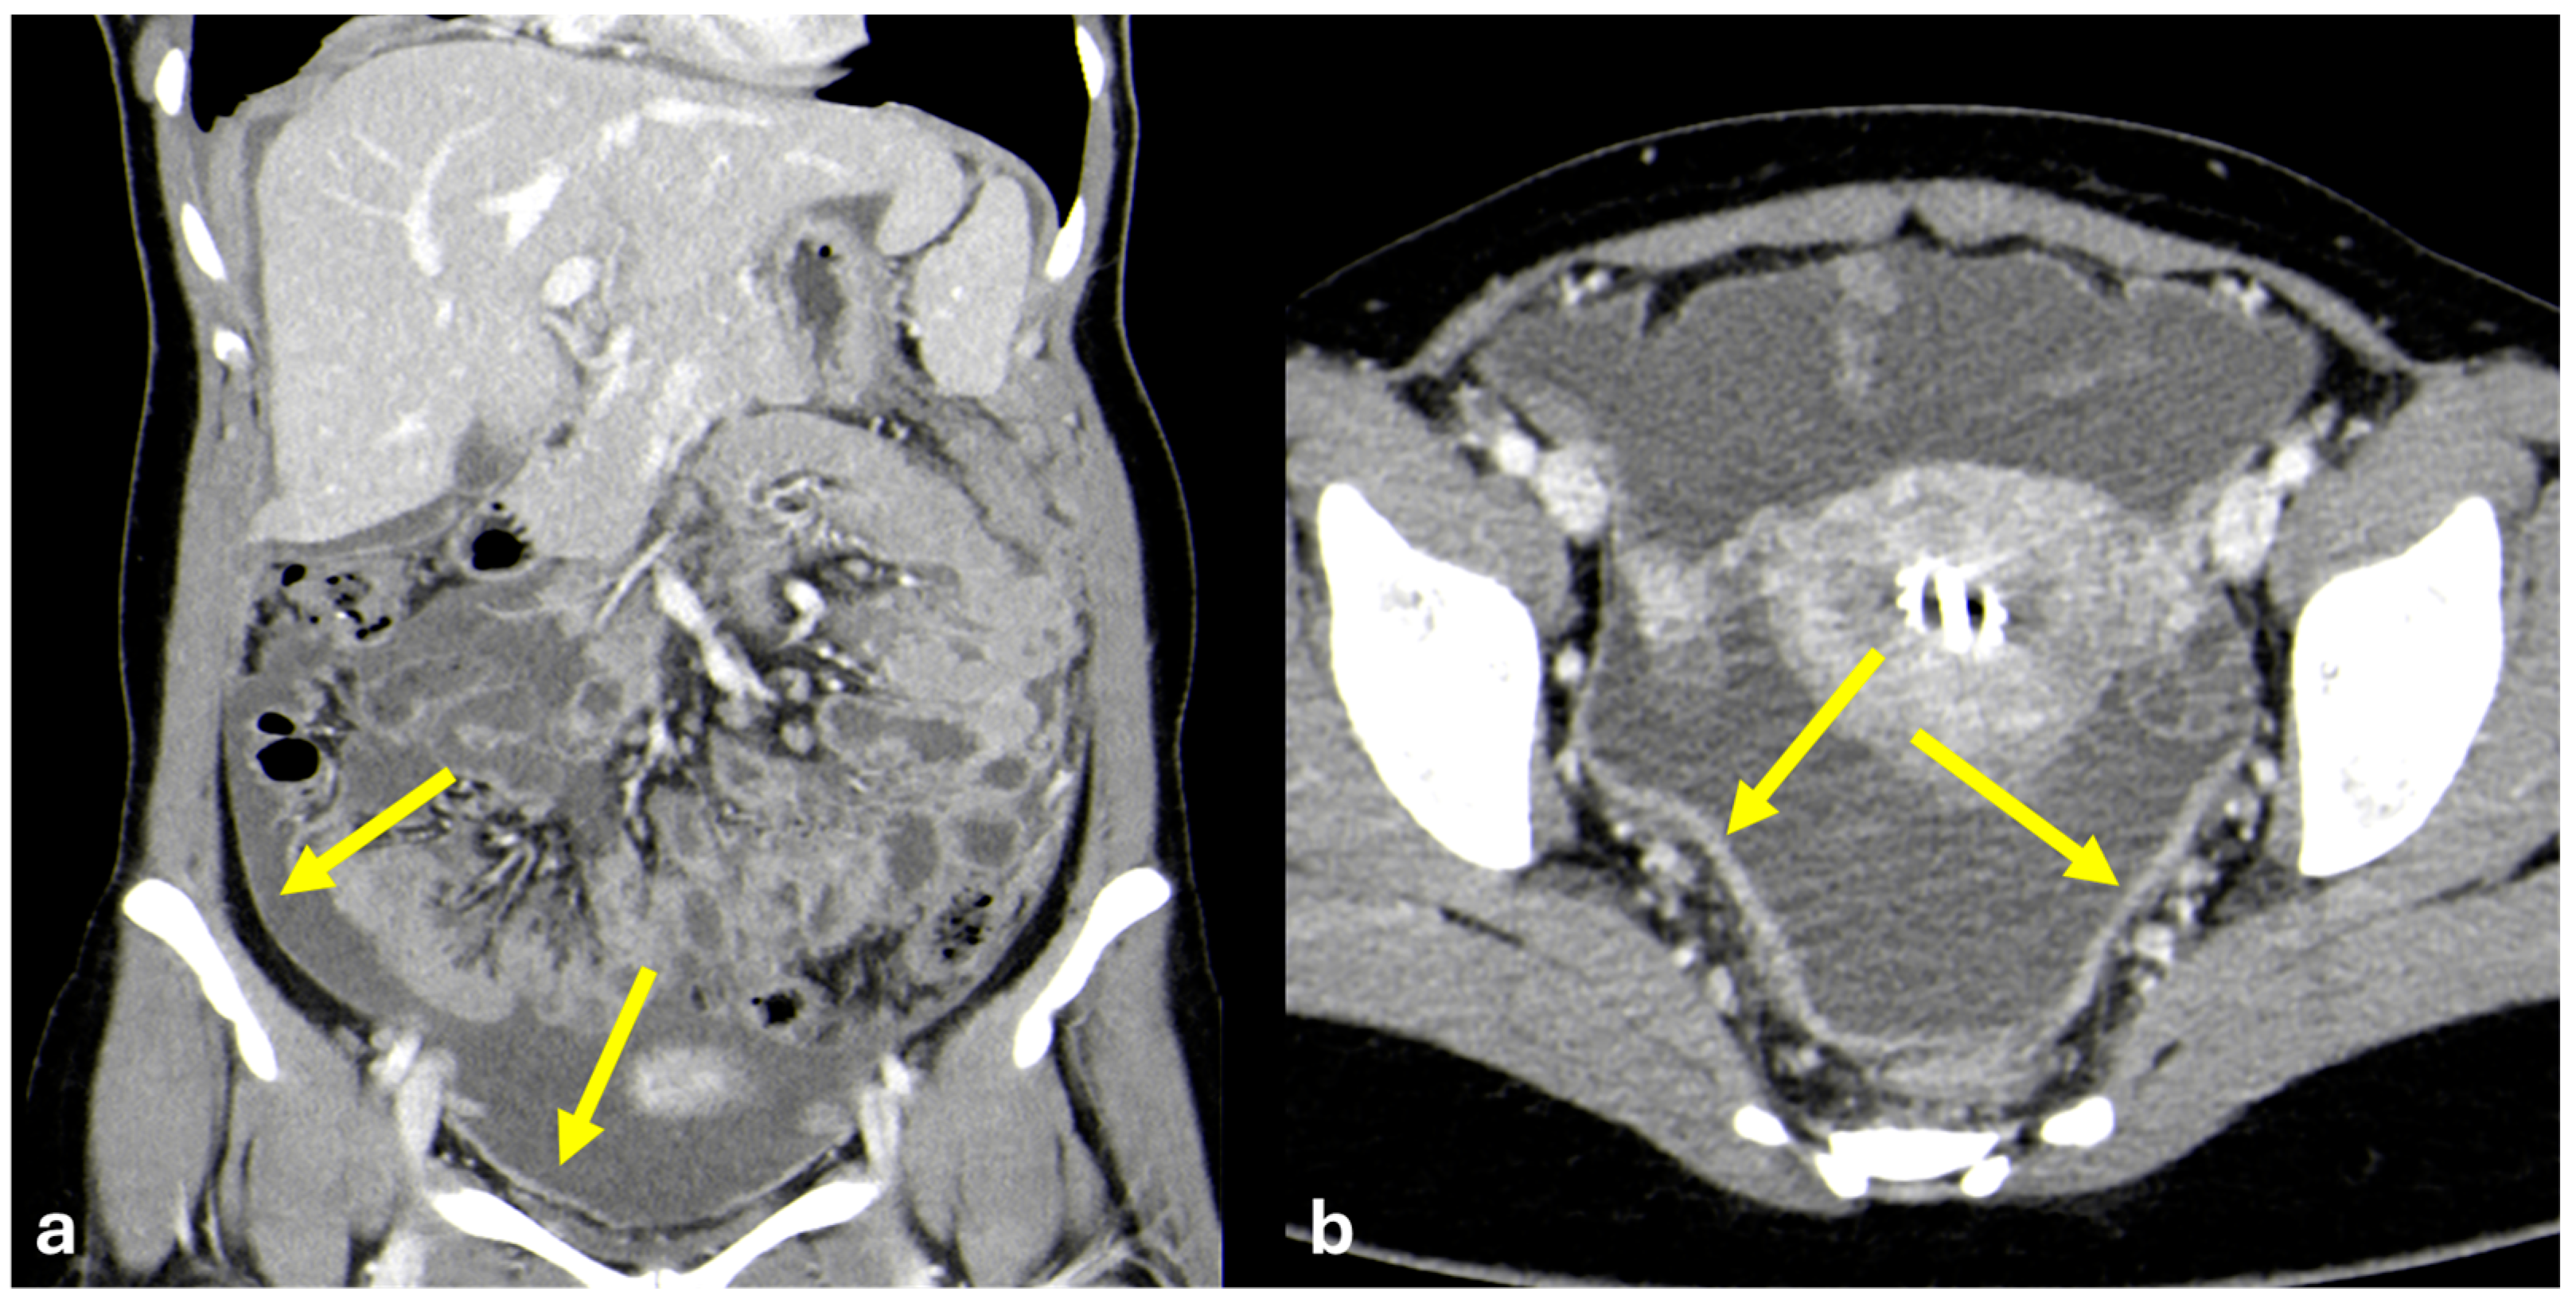

- Plaque pattern: confluent nodular plaques, typically involving the lower surface of the right diaphragm (Figure 3);